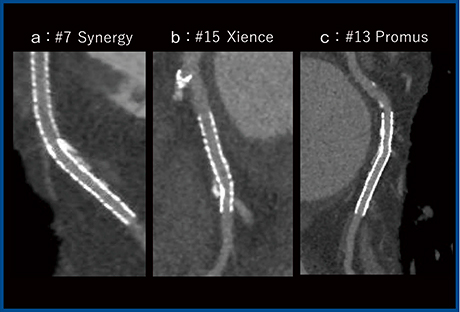

PCIに用いられる3.0mm未満の薬剤溶出ステント(DES)には,さまざまな素材,径が存在する。図3は,2.25mmのステントで,aはSynergy(プラチナ・クロム合金),bはXience(コバルト・クロム合金),cはPromus(プラチナ・クロム合金)である。素材の違いにかかわらず,小径の2.25mmでも内腔がしっかりと描出できていることがわかる。

図3 Aquilion Precisionでの小径ステントの描出:2.25mm